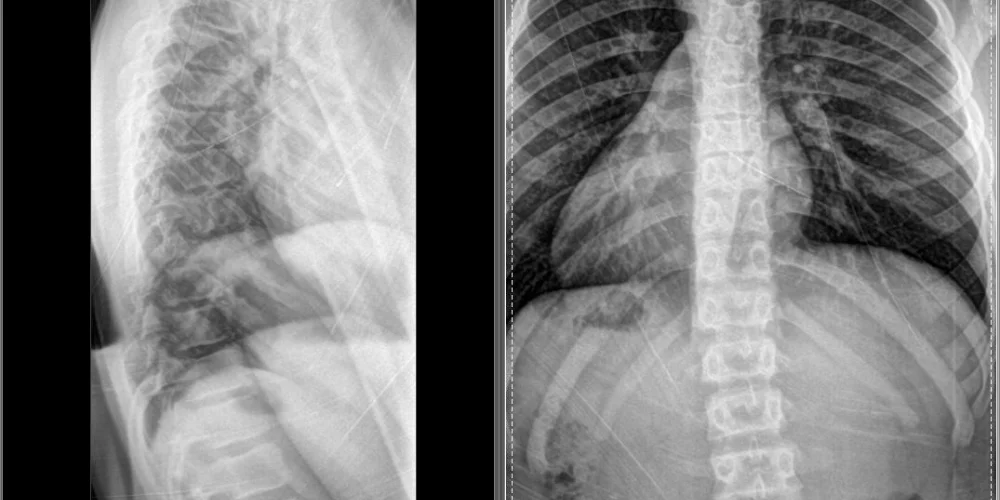

Full-spine x-ray films allow us to precisely analyze the entire structure of your spine and correlate these biomechanical findings with your entire examination.

This enables the most precise adjustment to achieve the best corrective results.

X-ray’s also rule out any congenital malformations, disease processes, and / or fractures.